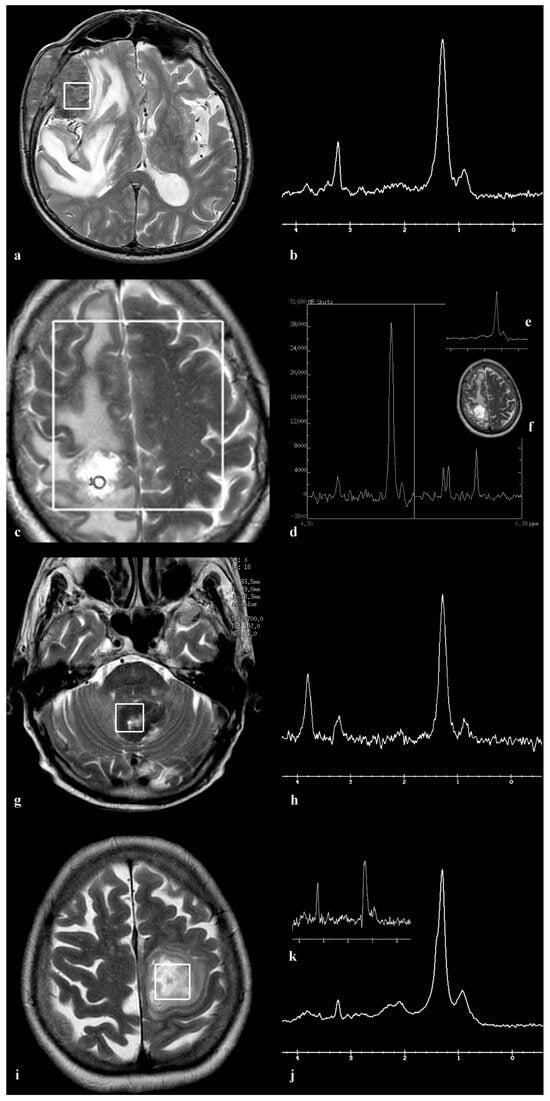

3.3. Patient 3

3.4. Patient 4

3.5. Patient 5